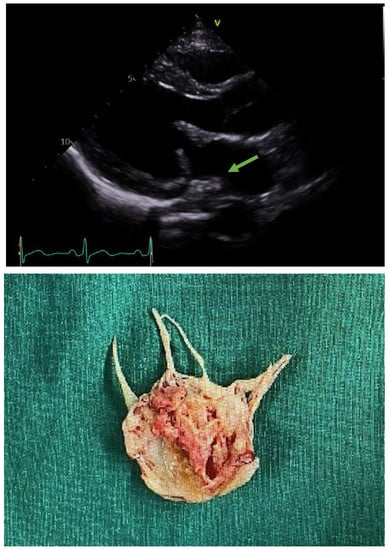

6.2. Infective Endocarditis Was Found on Examination and Thoracic Surgery Was Performed

- For infective endocarditis with vegetation over 10 mm, rapid valve surgery should be considered.